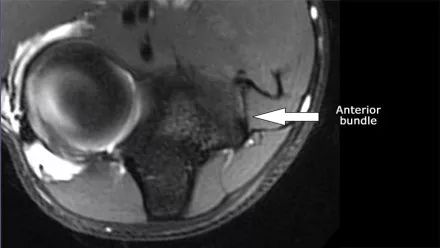

在研究韧带时,尤其是UCL,始终使用轴向图像。如果你看内侧上髁,你会发现后束是一个薄的结构(蓝色箭头)。注意在肘管内的尺神经。

后束形成肘管隧道的地板。支持带覆盖肘管。请注意,前束更厚(白色箭头)。您可以看到前韧带和后韧带之间的区别,即使它们形成一条韧带。走向远端,我们会看到它们合并在一起以附着于崇高的结节。

在下面轴向图像上,我们很好地看到前束是o.k. (红色箭头)。它旁边只有一些水肿。